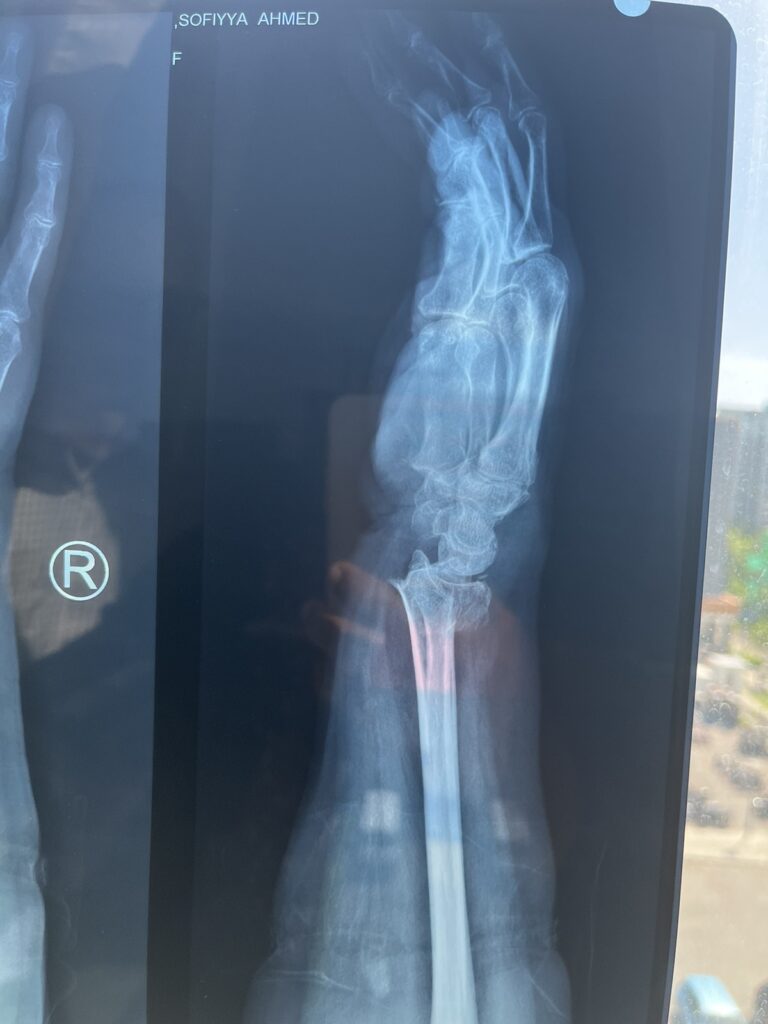

އެމްޓީސީސީ ބަހަކުން ސައިކަލެއްގައި ޖެހި އިއްޔެ ހިނގި އެކްސިޑެންޓްގައި އަނިޔާވި އުމުރުން ދުވަސްވީ އަންހެންމީހާގެ އަތުގެ ދެ ތަނަކުން ބިންދައިގެން ގޮސް މިއަދު އޮޕަރޭޝަން ކުރާނެ ކަމަށް އާއިލާއިން ބުނެފިއެވެ.

ނަމަވެސް އާއިލާއިން ބުނީ އެކްސިޑެންޓް ހިނގާފައިވަނީ ހޮނިހިރު ދުވަހުގެ 12:15 އެހާއިރު ކަމަށެވެ. އަދި އެކްސިޑެންޓްގައި ބޮޑަށް އަނިޔާވެފައިވަނީ ސައިކަލު ފަހަތުގައި އިން 66 އަހަރުގެ މަންމަ އަށް ކަމަށެވެ.